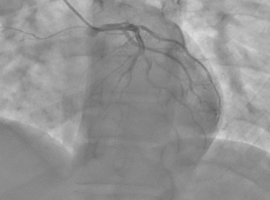

Resurrecting the Heart: Complex Coronary Reconstruction on Central VA ECMO for Immediate Post-CABG STEMI

Volume 5, Issue 4

Spontaneous Coronary Artery Dissection: Review of Current Management Strategies